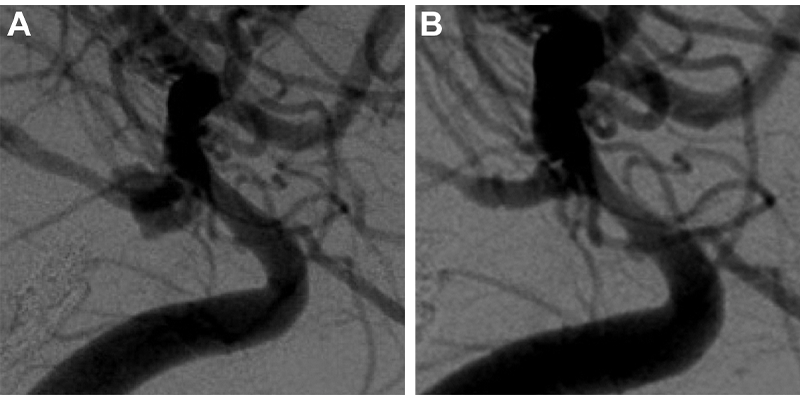

Digital subtraction angiography images show posterior communicating artery aneurysm (A) before and (B) at last follow-up after Woven EndoBridge device placement.

Adeeb et al, Radiology 2022; 000:1–11 ©RSNA 2022